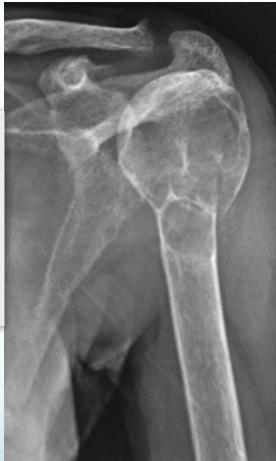

X-rays

- Which bone, and which site in bone?

- Solitary or multiple?

- Bone forming or bone eating?

- Margins: well-defined or ill-defined?

- Calcifications in the lesion?

- Is cortex eroded or destroyed?

- Is there periosteal new bone formation?

- Soft tissue extension?